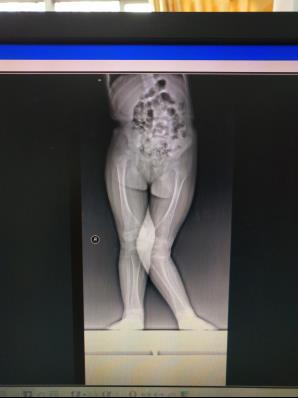

儿童下肢畸形

儿童下肢膝外翻畸形应用“8”字钢板骨骺阻滞术,效果满意